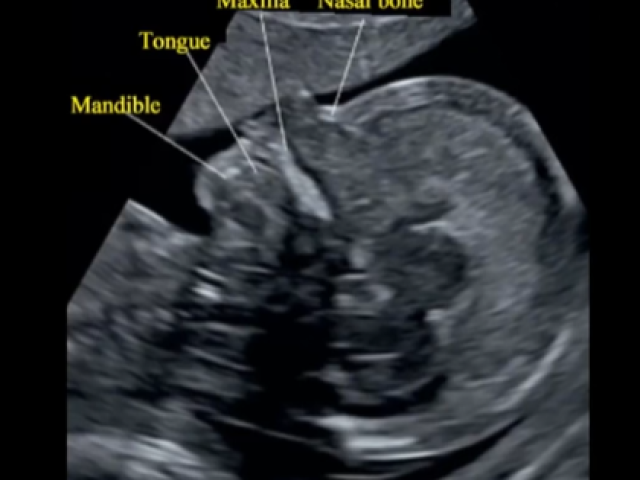

Comprehensive Ob/Gyn Ultrasound Education Modules

Normal System Anatomy and Associated Abnormalities (9 CMES) $13.49 Click Here